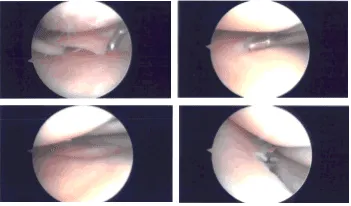

A lateral arthroscopic entry portal was made. The arthroscope was entered. The Medical entry portal was made with the use of a spinal needle. Examination of the medial tibiofemoral compartment showed flap tear of the posterior horn as well as body of the medial meniscus.

Debridement was done with the use of biter as well as shavers. The meniscus was debrided to a balanced margin. There was an interior flap of the margin of the periphery of the body of the meniscus also. This was also removed with the use of shavers.

There was a grade 1 to grade 2 osteochondral lesion of the medial femoral condyle which was debrided with use of shaver and ablator. Examination of the intercondylar notch showed degenerative ACL but intact.

Examination of the lateral tibiofemoral compartment showed intact femoral cartilage. There was fraying and tear of the medial margin of the lateral meniscus which was debrided with the use of shaver and biters.

Examination of the patellofemoral compartment showed grade 1 to grade 2 tear of the lateral facet of the patella which was debrided again with the shaver. There was no osteochondral lesion on the trochlea. The final picture was taken and saved.

Intraoperative Arthroscopy Images